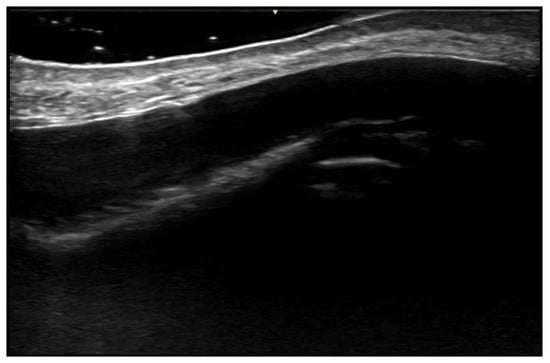

- Ranosz-Janicka, I.; Lis-Święty, A.; Skrzypek-Salamon, A.; Brzezińska-Wcisło, L. An extended high-frequency ultrasound protocol for assessing and quantifying of inflammation and fibrosis in localized scleroderma. Ski. Res. Technol. 2019, 25, 359–366. [Google Scholar] [CrossRef] [PubMed]

- Khorasanizadeh, F.; Kalantari, Y.; Etesami, I. Role of imaging in morphea assessment: A review of the literature. Ski. Res. Technol. 2023, 29, e13410. [Google Scholar] [CrossRef] [PubMed]

- Etesami, I.; Azizi, N.; Sabrinejad, R.; Montazeri, S.; Kamyab, K.; Nasimi, M.; Mahmoudi, H.; Khorasanizadeh, F.; Wortsman, X. Sonographic skin features and shear wave elastography in distinguishing active from inactive morphea lesions: A case-control study. J Am Acad Dermatol. 2025, 92, 155–157. [Google Scholar] [CrossRef] [PubMed]